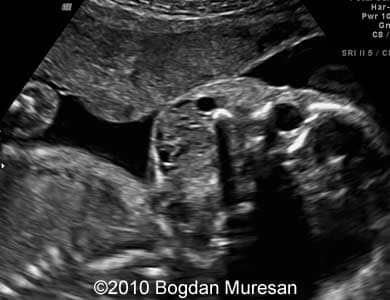

Images 1- 4: 23 weeks, parasagittal view of the cervical region, note multilocular cystic tumor located below the mandible.

Lymphangioma_Muresan_3